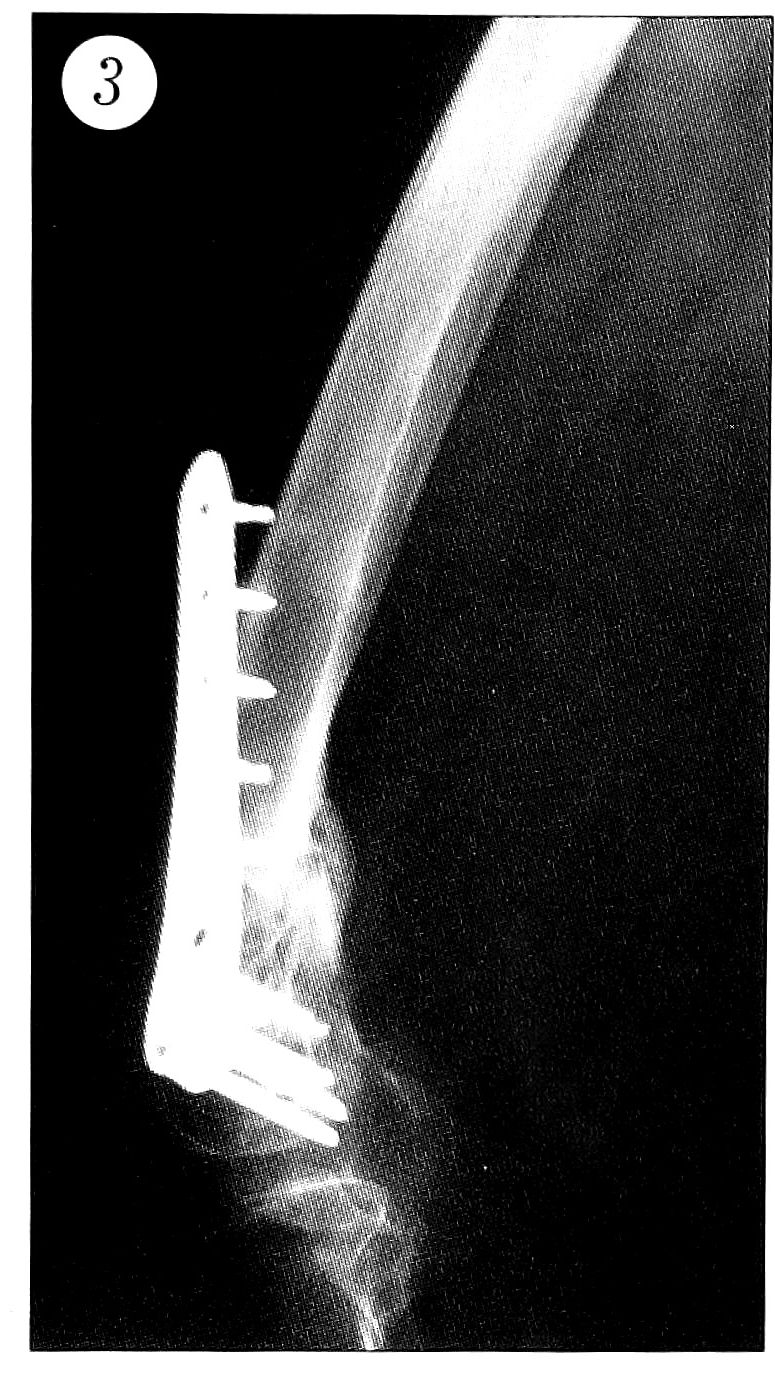

Переломы типа 33А диагностированы у 16 пациентов,33В — у 7 и 33С — у 12. В 30 случаях переломы были закрытыми, в 5 — открытыми. Большинство оперативных вмешательств выполнено в течение первых 48 ч с момента травмы. Для остеосинтеза чаще всего использовали пластину средней длины «9 отверстий». В 4 случаях пластину пришлось удалить в сроки около 2 мес после операции. В двух случаях это было связано с развитием септического артрита. У одного больного проксимальные винты пластины из-за контакта с гвоздем «Gamma» на уровне его дистального конца спровоцировали отталкивание пластины от кости (рис. 2), что потребовало повторной операции — реостеосинтеза. В четвертом случае пластина была установлена со значительным передним наклоном, вследствие чего отсутствовал контакт проксимальных винтов с костной тканью (рис. 3); тем не менее перелом сросся, но пластину со временем пришлось удалить, так как она причиняла боль при разработке движений в коленном суставе.

Рис 3. Плохая репозиция отломков и, как следствие, неправильное положение имплантата.